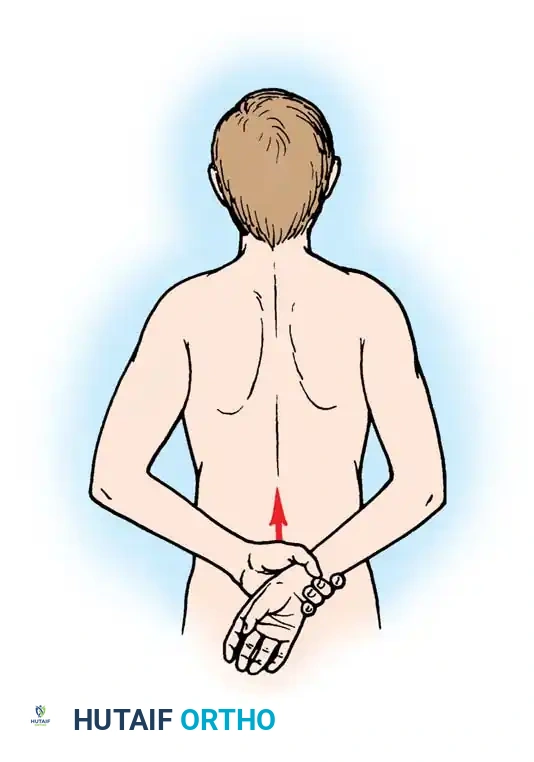

Dislocate the humeral head anteriorly through external rotation and extension. Remove peripheral osteophytes to identify the true anatomical neck. The humeral cut is made along the anatomical neck, typically at 30 degrees of retroversion and 45 degrees of inclination.

Broach the humeral canal sequentially. Assess the trial components for stability, ensuring 50% posterior translation on the "drawer test" and no superior escape. Implant the final prosthesis (press-fit or cemented based on bone quality).